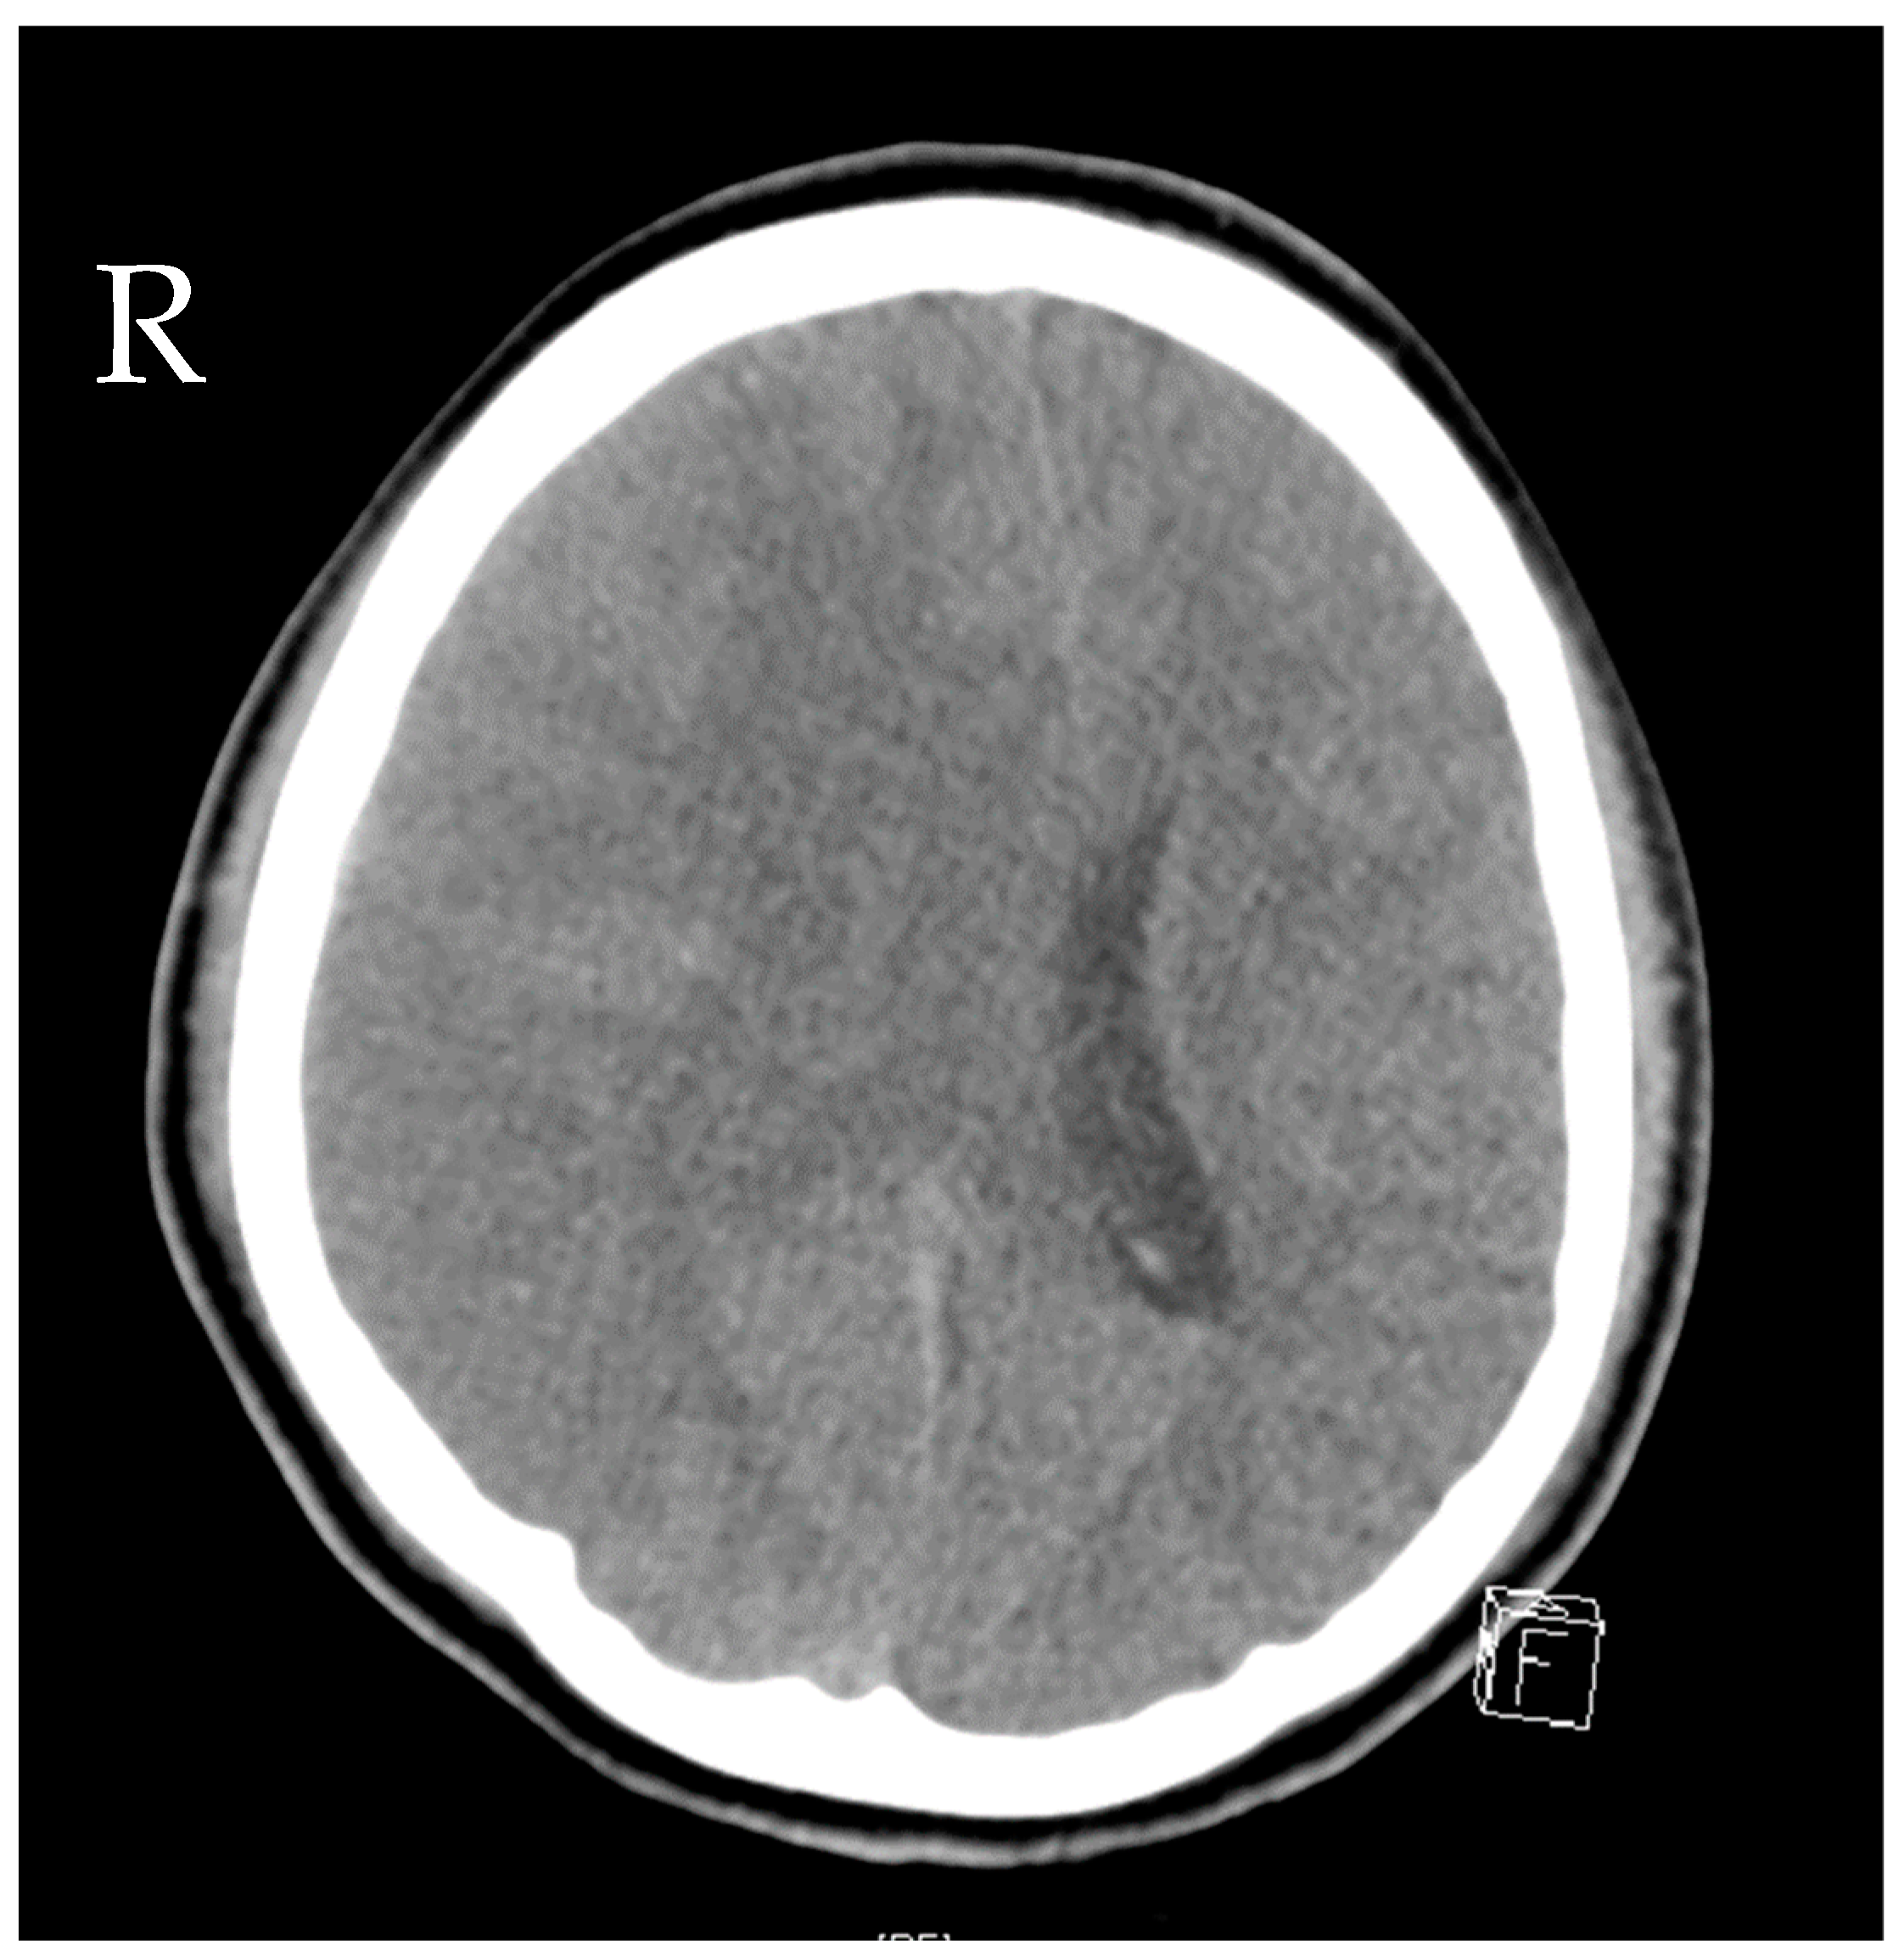

2. Case Presentation